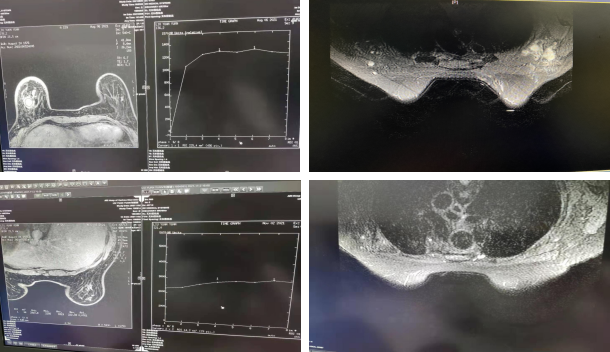

乳腺MR(2021-11-03):右乳ca治疗后,右乳腺体T2W1信号不均,DWI呈高信号,ADC值为2.01*10-3mm2/s。外下象限可见斑片影,边界不清,增强后强化不明显。双腋窝未示明显肿大淋巴结。胸骨右旁示DWI呈高信号小结节样影。

图7.2021-08-06MR结果(上)vs2021-11-03MR结果(下)